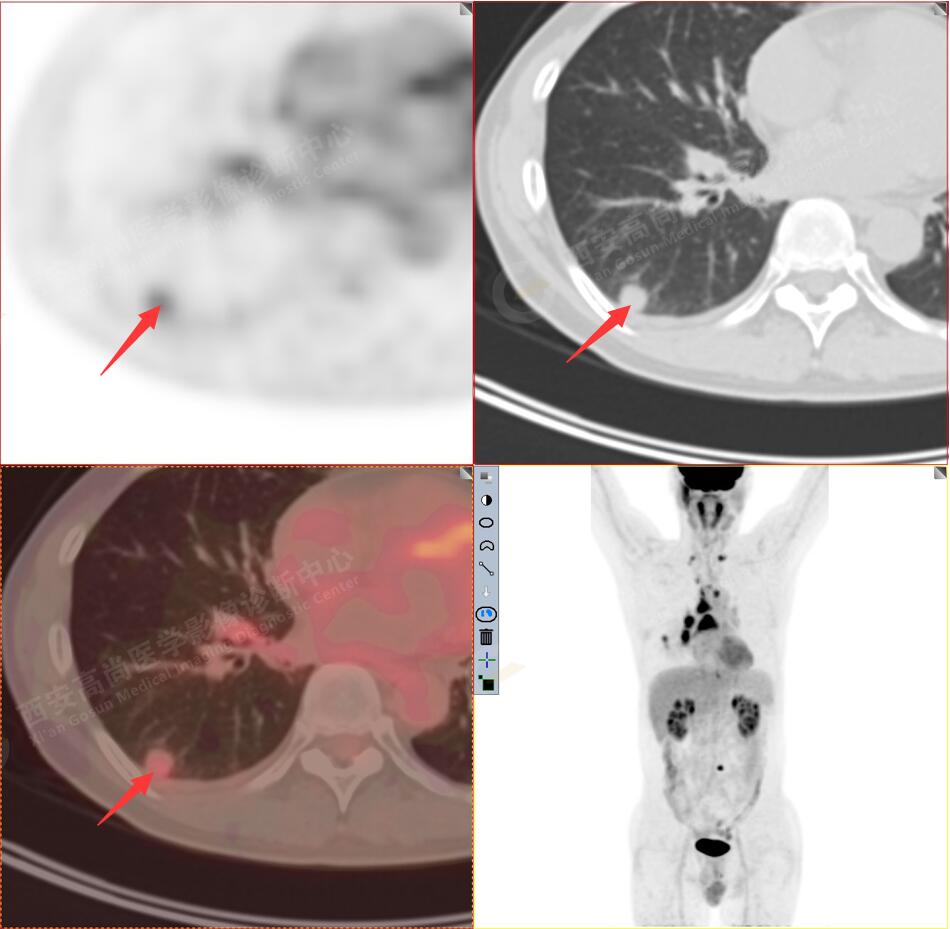

2.以下為全身多發(fā)轉(zhuǎn)移灶

2.雙肺多發(fā)高密度小結(jié)節(jié)灶(最大徑約0.7cm),部分較大結(jié)節(jié)呈FDG代謝略增高,均考慮為轉(zhuǎn)移性病變。

3.右側(cè)肺門、縱隔(1L、1R、3A、4、6、7組)及雙側(cè)鎖骨上多發(fā)腫大淋巴結(jié),呈不同程度FDG代謝異常增高,考慮為淋巴結(jié)轉(zhuǎn)移。

4.右后胸膜輕度增厚,形成多個(gè)條狀軟組織病變,呈FDG代謝輕度異常增高,考慮為轉(zhuǎn)移性病變;右側(cè)胸腔微量積液。